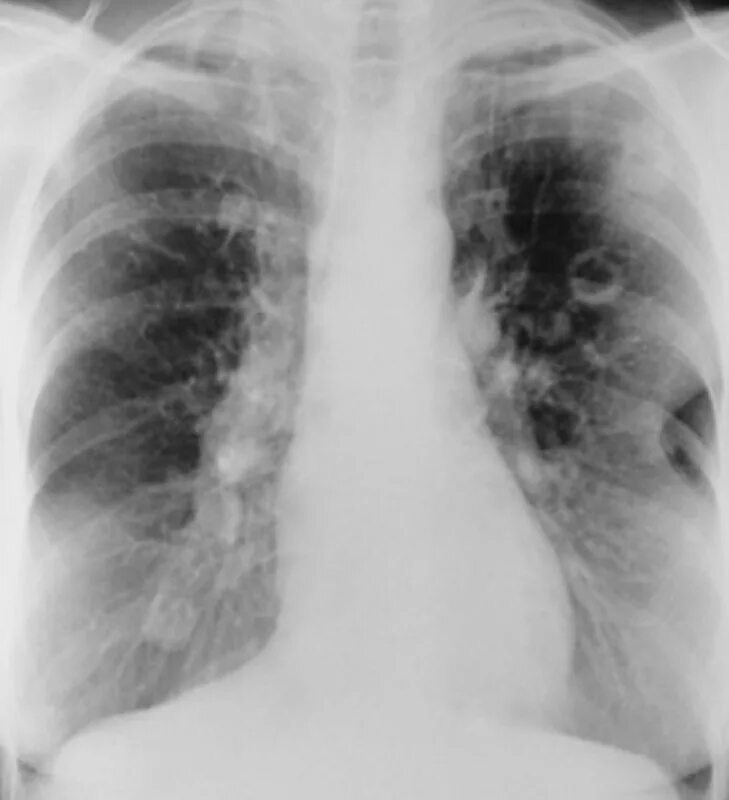

Метастазы в легких терапия